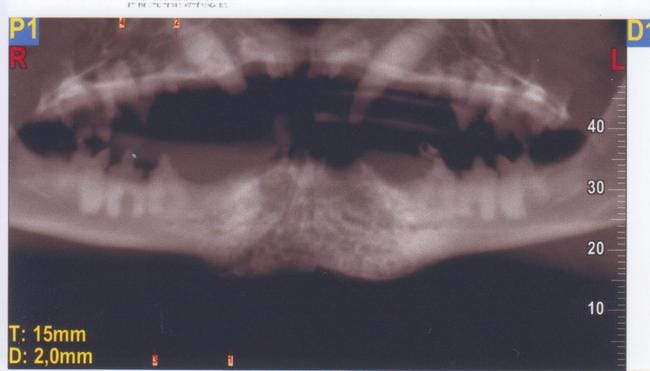

Cône Beam New Tom 5G

Technique : Examen des mâchoires en section axiale ; images natives de 0,1mm ; reconstruction MPR et 3D 0,1mm temps d’exposition total : 7.3s ; mAs : 23.08 ; kV 110kV ; CDTi/V (dose délivrée / surface exposée) : 3.27 mGy

Description

Mise en évidence d’une masse homogène se développant dans la base du menton avec néoformation osseuse de type proliférative.

Centre de la lésion au niveau de l’alvéole de la canine gauche absente et extension hauteur de PM3 pour la mandibule gauche et Pm2 pour la mandibule droite.

Limite carcinologique appréciée (5mm) en mésial des carnassières.